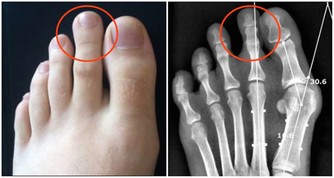

芝麻莖葉飲慢性風濕性關節炎

芝麻葉、莖各250克,洗淨,煎水200毫升。

溫服,常服可防慢性風濕關節炎復發。